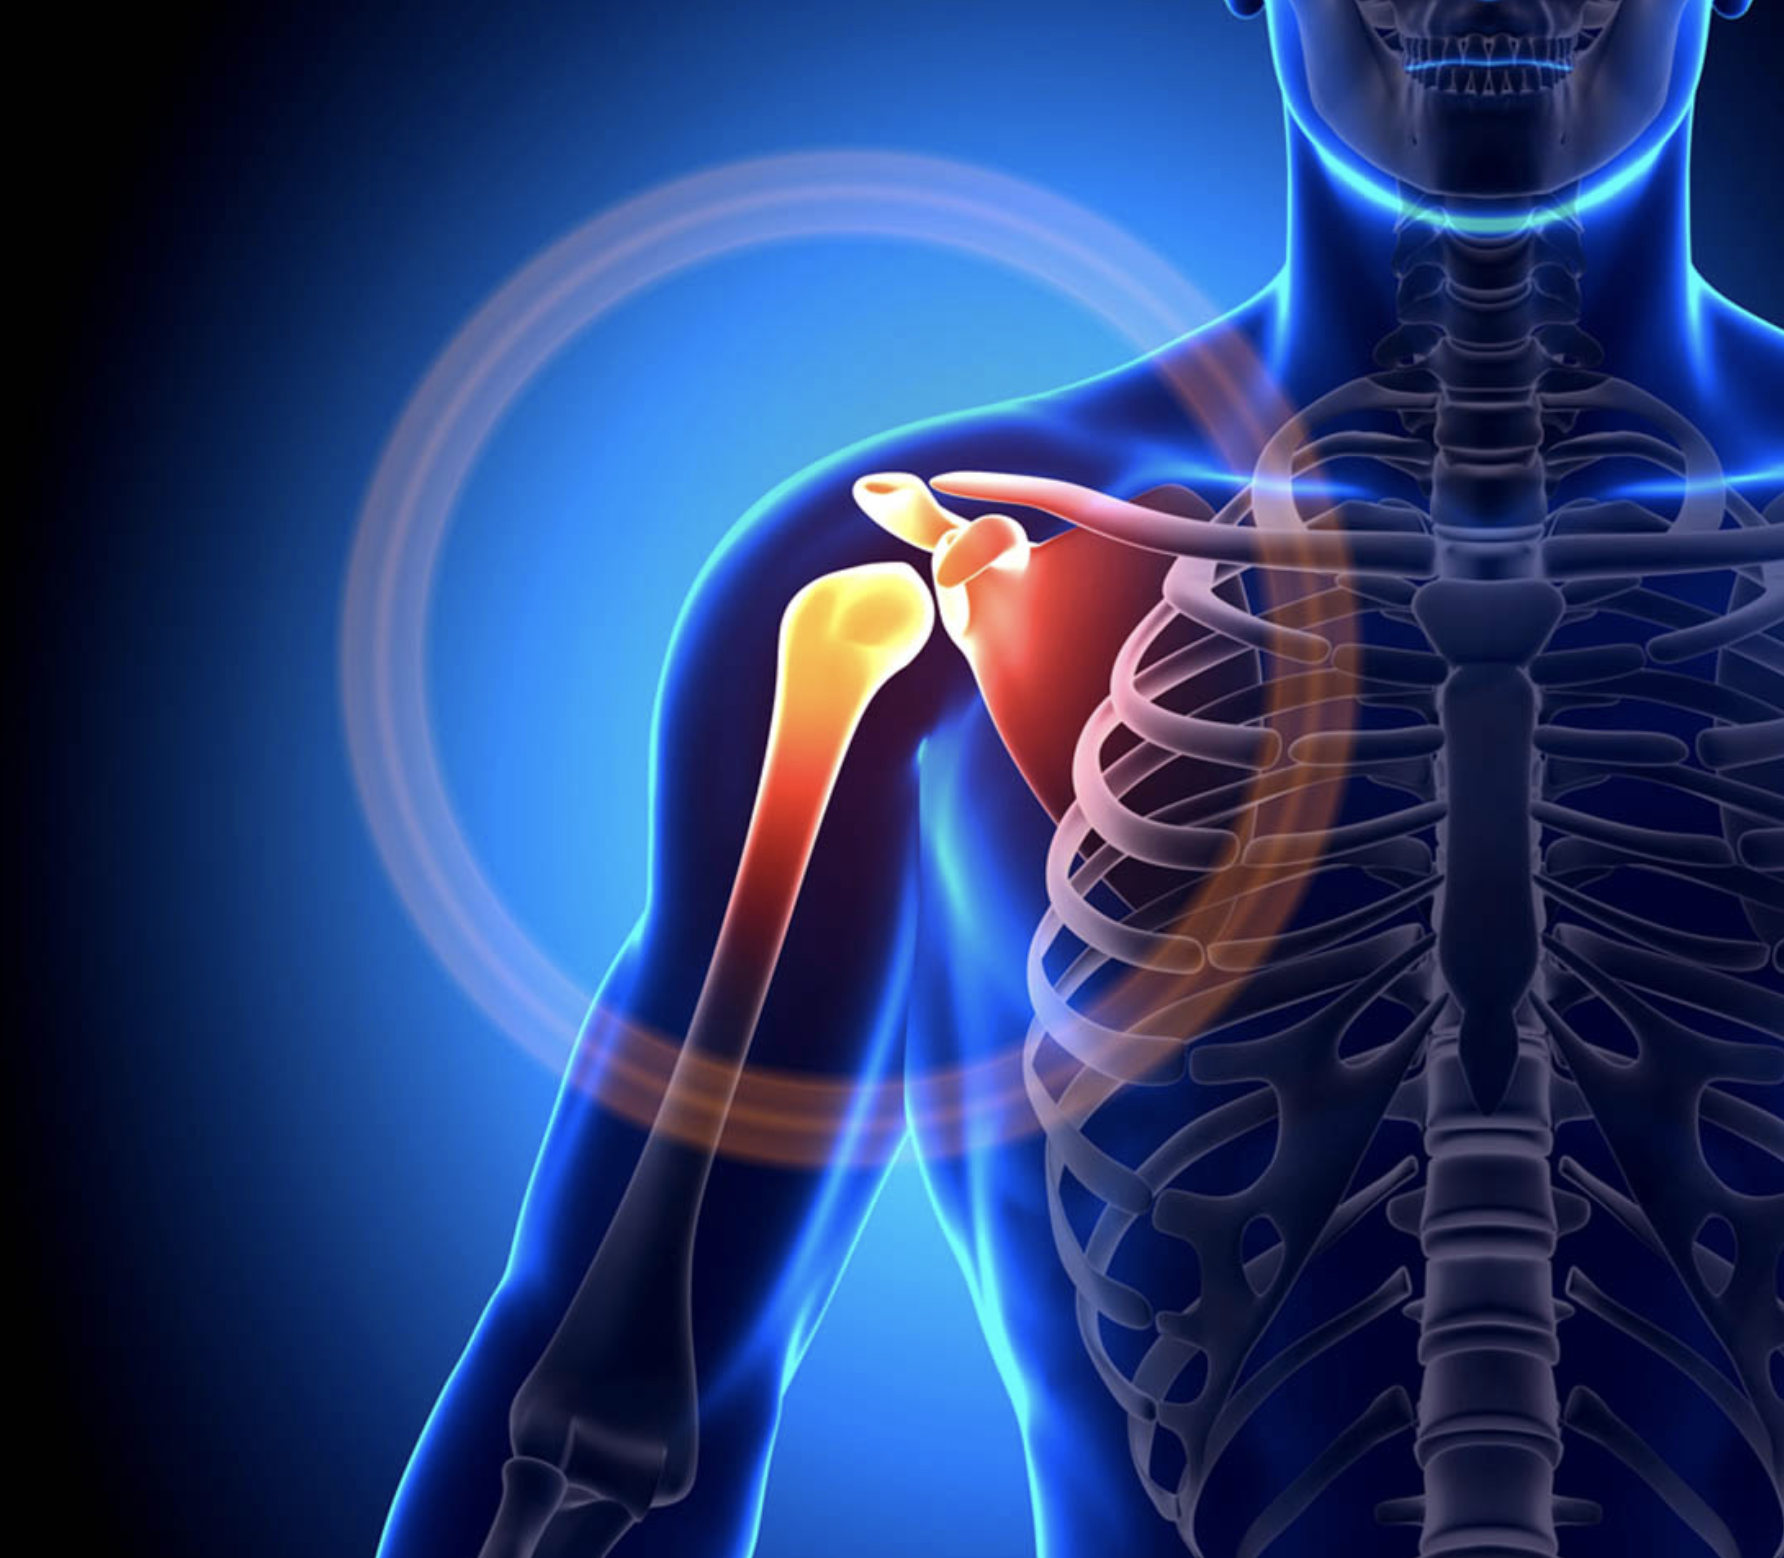

Your Expert in Comprehensive Joint Care.

Proven Expertise in Restoring Mobility, a Track Record of Excellence, and Advanced, Compassionate Care for Optimal Orthopedic Health